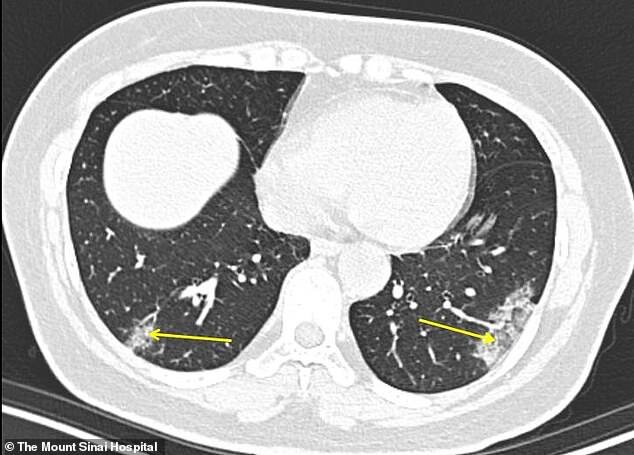

تشخیص کروناویروس ۴روز زودتر از پیش امکان‌پذیر شد

ICTPRESS - پژوهشگران اخیرا اعلام کرده‌اند با کمک سی‌تی اسکن می‌توان بیماری مهلک کروناویروس را چهار روز زودتر تشخیص داد.